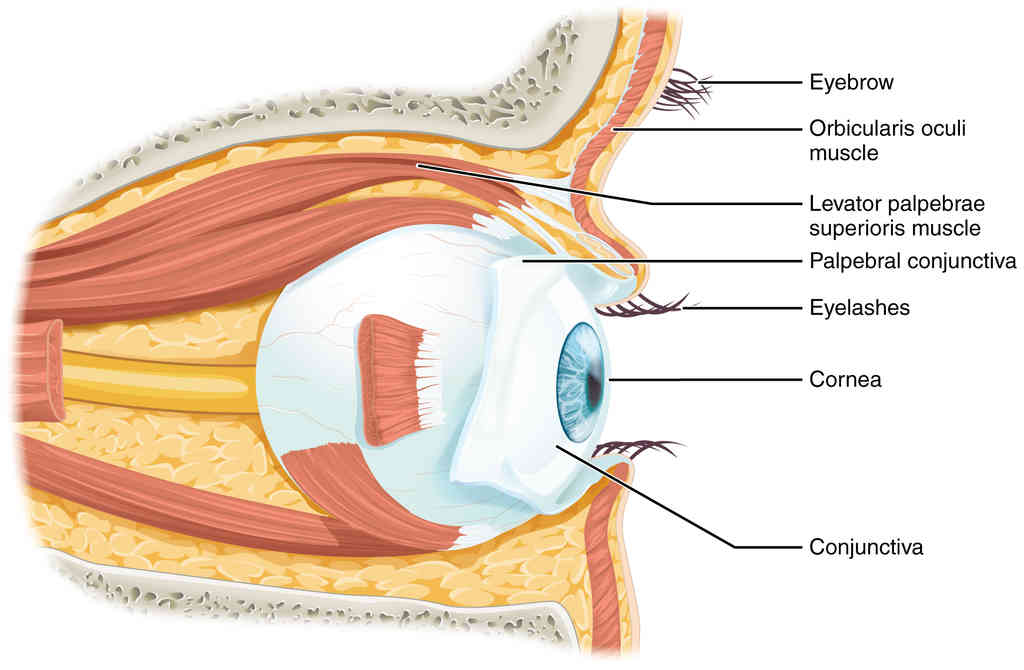

This page is under construction. For now, it is just a resource of the images found in the OpenStax Anatomy and Physiology Handbook. It wil slowly change into a revision tool. Each slide has a number. Use this to refer to the slide. When completed, it will have an unlabelled section, with labelled slides in parallel. On the unlabelled slides, write your answer and use the labelled slide to assess yourself. Keep track by also noting the number on each slide. Improvement at each attempt is important, more so than full marks on a first attempt.